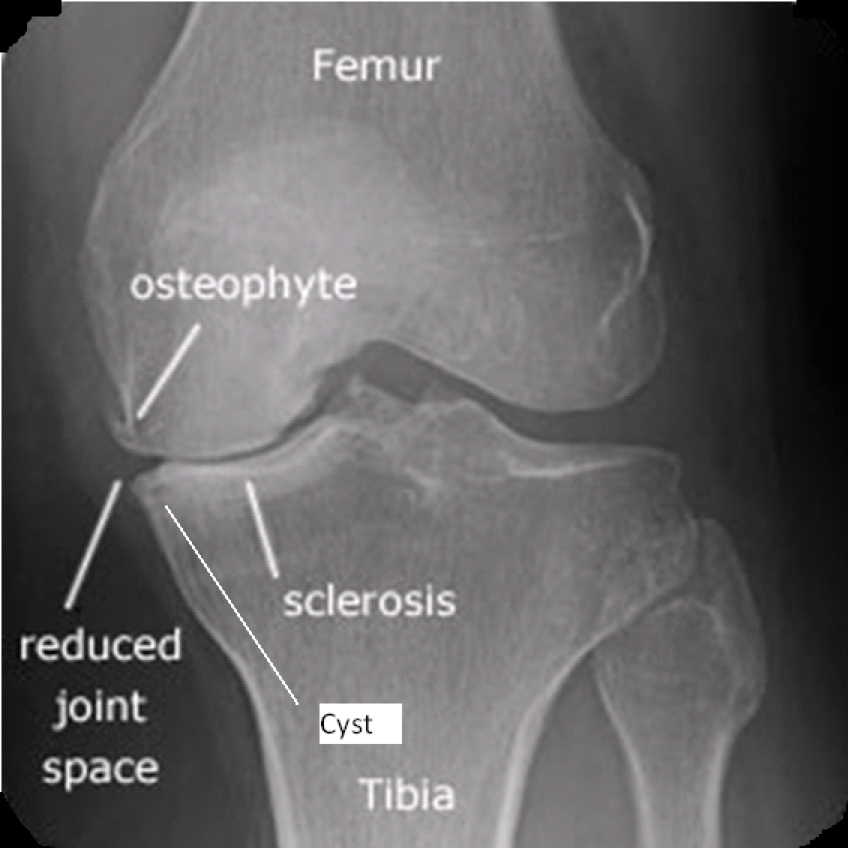

- Radiography

- 4 Radiographic Criteria of Osteoarthritis

- Diminished joint space

- Bony sclerosis

- Osteophytes

- Subchondral cyst